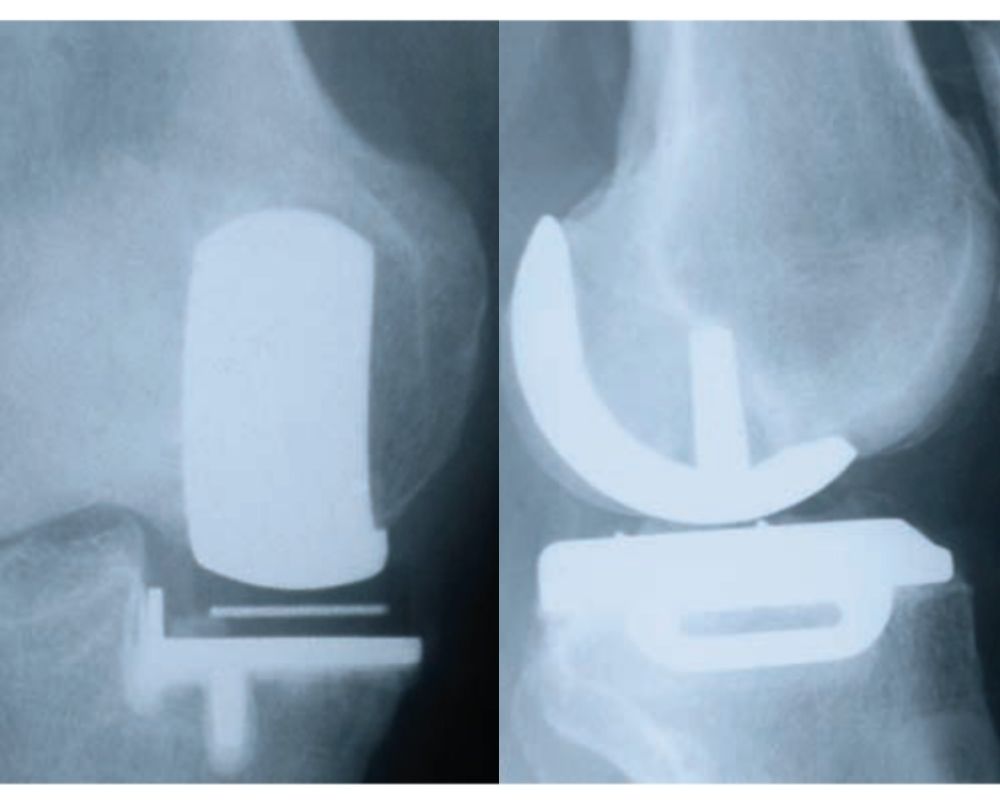

Rx preoperatoria

Rx postoperatoria

In casi selezionati può essere utile l’impianto di una protesi monocompartimentale, considerata la vera protesi di ginocchio mininvasiva. Prevede infatti la sostituzione del solo compartimento danneggiato con componenti protesiche di superficie che rivestono il condilo femorale e l’emipiatto tibiale (mediale o laterale).

Questo tipo di protesi è indicata nell’osteonecrosi del condilo femorale o dell’emipiatto tibiale e nell’artrosi monocompartimentale (che interessa solo una parte del ginocchio, quella mediale o quella laterale).

L’intervento prevede un’incisione di circa 7-8 cm; il decorso postoperatorio è meno impegnativo rispetto a un’artroprotesi totale e il recupero riabilitativo più veloce.